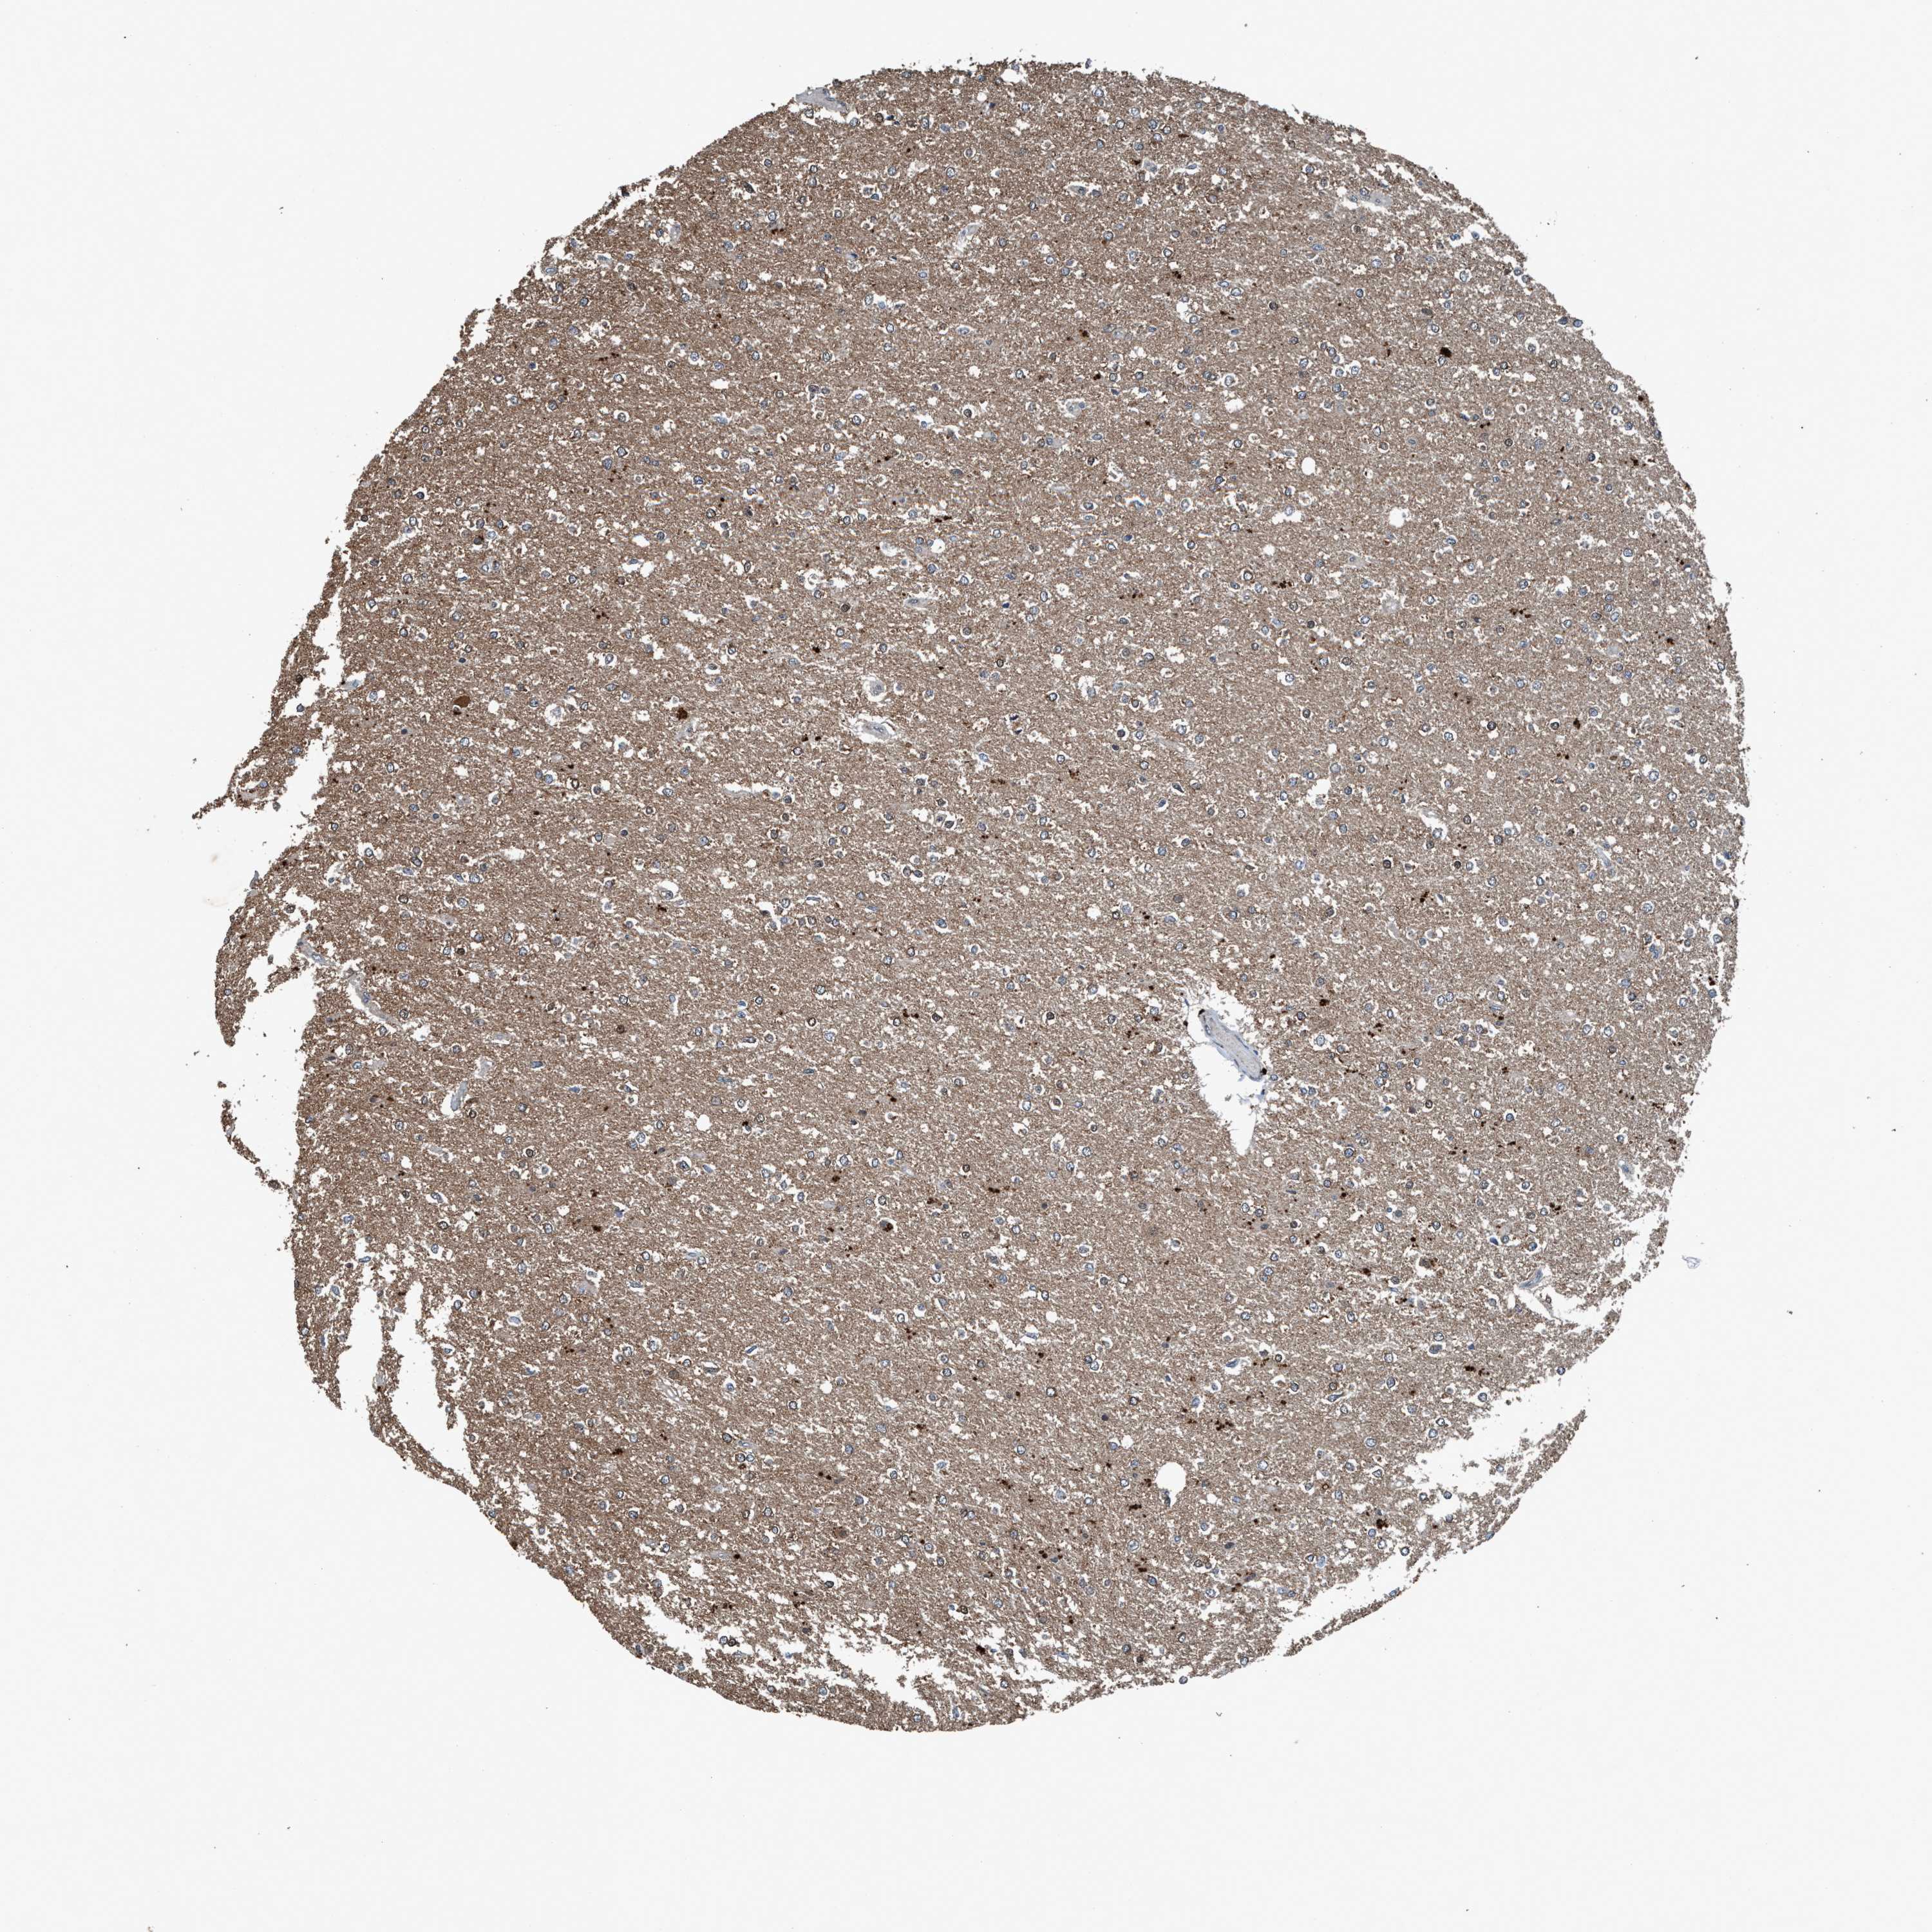

GLIOMA - Protein expressioni

A mouse-over function shows sample information and annotation data. Click on an image to view it in a full screen mode. Samples can be filtered based on level of antibody staining by selecting one or several of the following categories: high, medium, low and not detected. The assay and annotation is described here.

Note that samples used for immunohistochemistry by the Human Protein Atlas do not correspond to samples in the TCGA dataset.

Antibody stainingi

Antibody staining in the annotated cell types in the current human tissue is reported as not detected, low, medium, or high, based on conventional immunohistochemistry profiling in selected tissues. This score is based on the combination of the staining intensity and fraction of stained cells.

Each image is clickable and will lead to virtual microscopy that enables deeper exploration of all samples and also displays staining intensity scores, fraction scores and subcellular localization as well as patient and tissue information for each sample.

Antibody HPA064427

Antibody HPA075510

Antibody CAB021903

Glioma, malignant, Low grade

Glioma, malignant, High grade